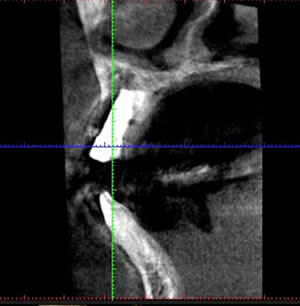

埋入後のレントゲン像です。前歯のインプラントは通常のレントゲンの他に、術後のCTが必要になります。

術後のCT像です。いいポジションにはいりました。(インンプラントを専門に行っている先生はわかるのですが一般の人には専門的でわかりませんね)。抜歯即時インプラントは難度の高いオペですが、患者さんにとって、切開しないため痛みもなく、当日仮歯も入り、オペの回数を減らせるのでとても有効な治療方法です。